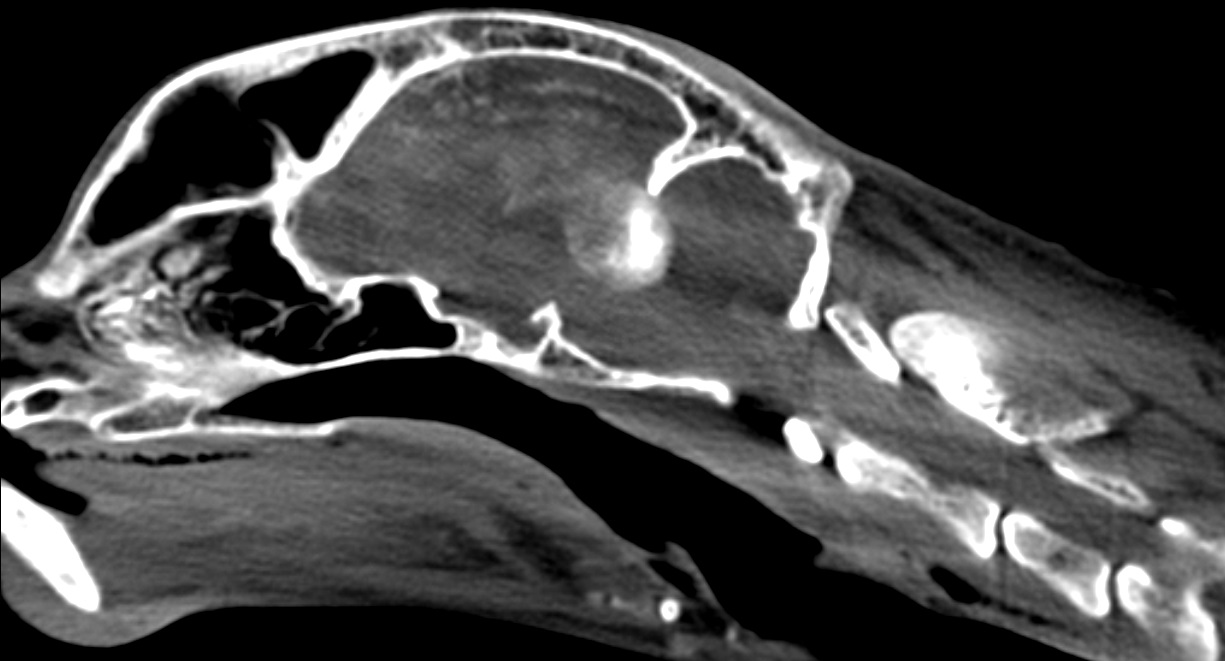

Для вашей собаки, как и для любого другого животного, в нашей клинике доступна компьютерная томография (КТ) — передовая диагностика, позволяющая выявить скрытые заболевания и патологии, включая новообразования и травмы. В отличие от рентгена и УЗИ, КТ — это послойное исследование, которое использует ионизирующее излучение для создания детализированной 3D-модели.

С помощью КТ мы можем изучить голову, шею, брюшную полость, конечности, а также органы, кости, суставы, головной мозг и спинной мозг. Для уточнения диагноза применяется контрастное вещество, позволяющее провести ангиографию или миелографию. Под контролем КТ возможна и биопсия.

Онкологические заболевания: КТ незаменима для выявления новообразований, определения их точной локализации, оценки распространенности и поиска метастазов в организме. Этот метод позволяет оценить, насколько тесно опухоль связана с органами, что критически важно при предоперационном планировании и решении о возможности ее удаления.

Заболевания нервной и сосудистой систем: КТ позволяет диагностировать опухоли головного и спинного мозга, гидроцефалию, аномалии сосудов (например, портосистемные шунты) и тромбозы.

Компьютерная томография использует рентгеновское излучение и отлично визуализирует плотные структуры, такие как кости и суставы. Она является предпочтительным методом при диагностике травм (переломов, кровоизлияний), а также для онкологического поиска и оценки состояния внутренних органов.